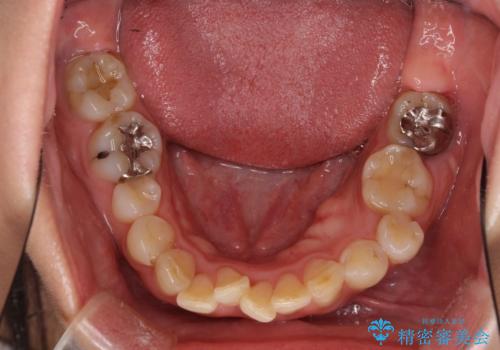

- 前歯のデコボコと前方に斜めに飛び出した前歯を気にして来院された患者様です。

口元の突出感はあまり気になっていませんでしたが、上下の前歯の前後差が大きかったため、上顎左右の第一小臼歯を抜歯し、上顎が裏側装置であるハーフリンガルにて矯正治療を行うこととしました。

咬合力が非常に強く、スペースがなかなか閉じなかったことと、上下の正中が著しくずれてきてしまったため、下顎左側小臼歯を途中抜歯することとなりました。

歯の動きが鈍く、矯正治療だけで4年以上の期間を要することとなりました。